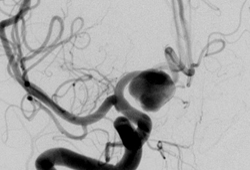

Cerebral angiogram showing aneurysm

From the personal collection of Dr M. Chen, Columbia College of Physicians and Surgeons